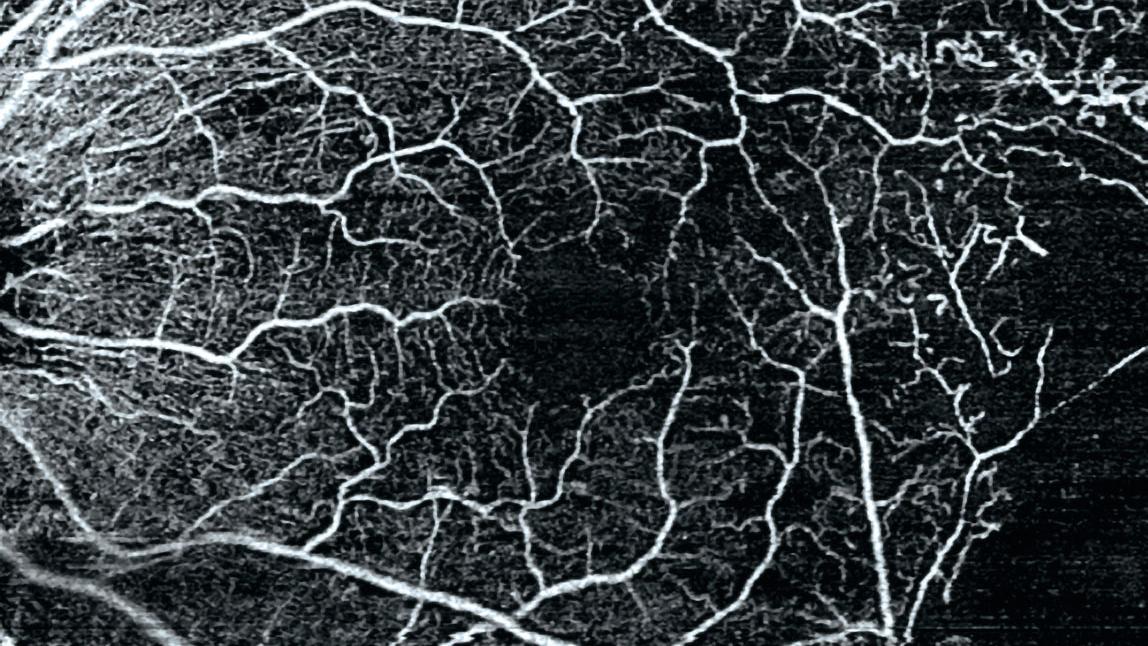

• 3x3 mm AngioPlex OCTA of proliferative diabetic retinopathy (PDR)

3x3 mm AngioPlex OCTA of proliferative diabetic retinopathy (PDR).

Image courtesy of Roger Goldberg, MD, Bay Area Retina Associates